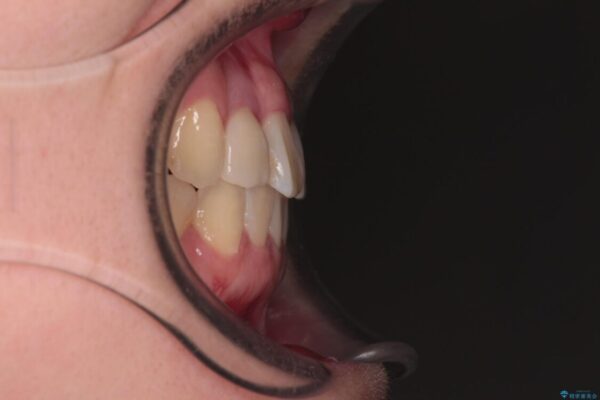

治療前

• 虫歯治療ついでに歯並びの後戻りを改善 インビザラインによる矯正治療 治療前画像